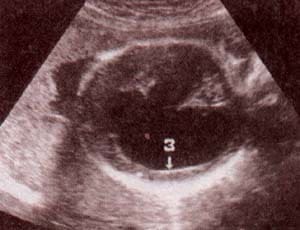

fig. 62. – (a). 18 semanas.corte sagital. |

fig. 62. – (b). corte transversal. estas formas de inicio precoz se hallan con frecuencia asociadas a anomalías cromosómicas. |